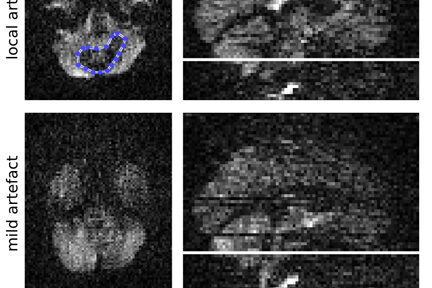

- Magnetic resonance imaging of the breast